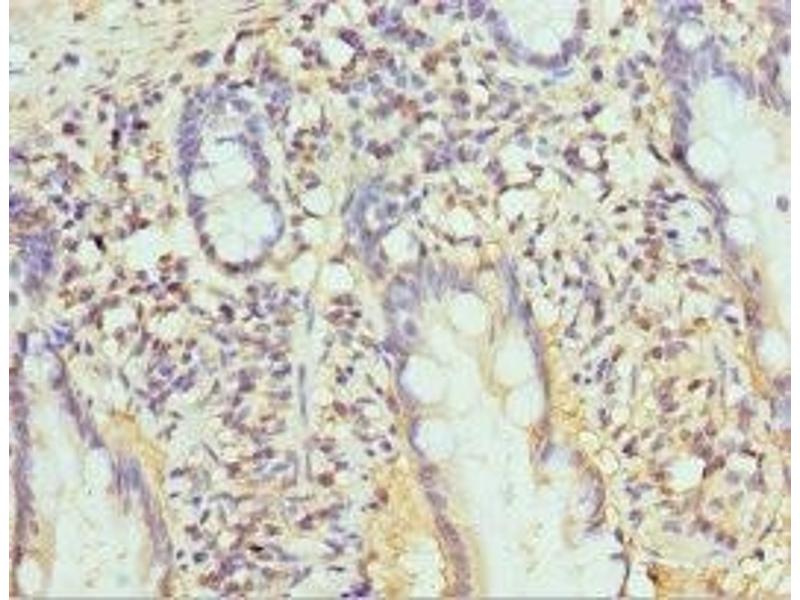

PSMB10 Reactivité: Humain IHC, ELISA Hôte: Lapin Polyclonal unconjugated

N° du produit ABIN7164972

328,90 €

Plus frais de livraison 40,00 € et TVA

100 μL (Autres quantités disponibles)

Destination: France

Envoi sous 11 à 15 jours ouvrables